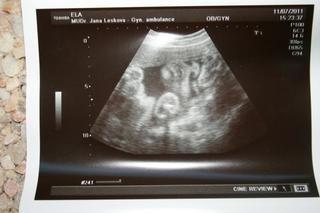

miraxíku ahoooj!!! 😵 téda chvilkku mi to ale dalo, to civění na obrázek abych to našla 😀 😨 ale našla 😉